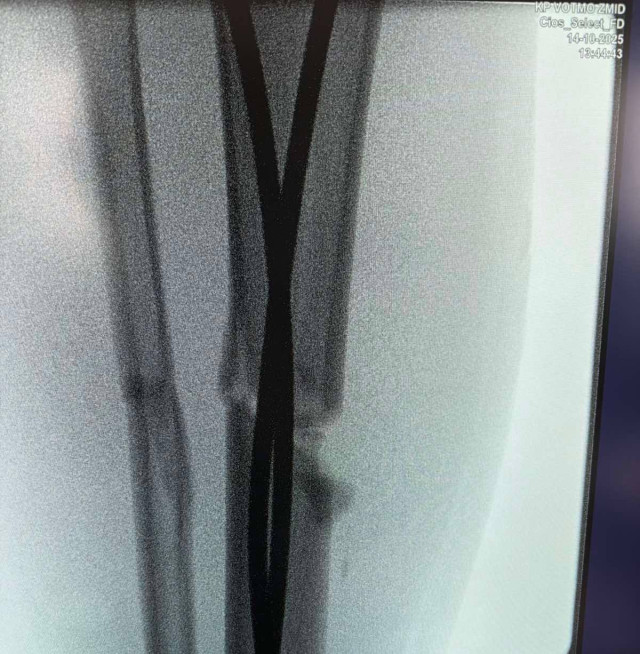

Наслідки падіння для 13-річного Максима – перелом стегнової кістки зі зміщенням і кісток гомілки.«Переломи дуже серйозні, – каже дитячий ортопед-травматолог Богдан Петерчук. – Попри це, завдяки інтрамедулярному остеосинтезу через два дні після операції Максим вже рухає ногою та швидко реабілітується. Оперативне втручання ми зробили через невеликі розрізи на стегні та гомілці».